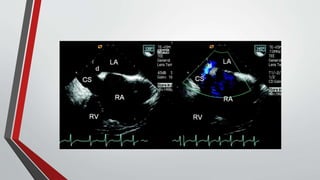

Echocardiography

• The functional importance of the defect can be estimated by the size of the right ventricle,

• The presence or absence of right ventricular volume overload (paradoxical septal motion),

• (less accurately) estimation of Qp/Qs.

• Indirect measurement of pulmonary artery pressure can be obtained from the Doppler velocity of the tricuspid

regurgitation jet.

• In ostium secundum atrial septal defects, : The mitral valve abnormalities consist of thickening and fibrosis of leaflets and

chordae tendineae .

• TEE permits better visualization of the interatrial septum and is usually required when device closure is contemplated,

partly to ensure that pulmonary venous drainage is normal

• ICE can be used instead of TEE during device closure to help guide insertion of the device, thereby reducing fluoroscopic

and procedural time and forgoing the need for general anesthesia.